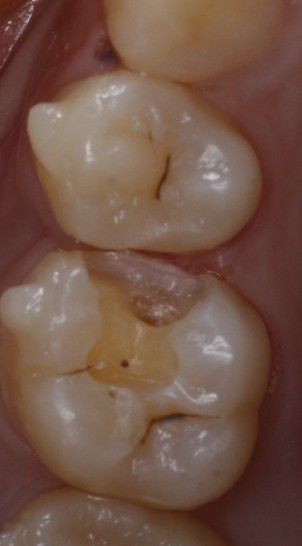

患者女,22岁。检查发现26近中邻面龋坏,色泽发黑,质硬冷测正常,余无特殊。治疗计划:去腐后嵌体修复。

食物嵌塞为细菌提供了良好的滋生环境,容易导致细菌大量繁殖,产生酸性物质,从而增加蛀牙的风险。最好是用嵌体修复,能更好的恢复牙体的形态和功能。增加了固位力,恢复正常的邻接关系,可以得到更好的清洁。通过德国西诺德 CEREC ,当时完成即可佩戴,患者满意。